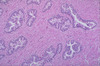

What tissue is this?

Prostate